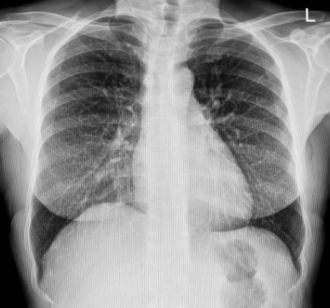

가슴 X-ray 한 번 촬영 시 피폭선량: 약 0.1~0.3mSv

흉부 X-ray | 약 0.1~0.3 mSv |